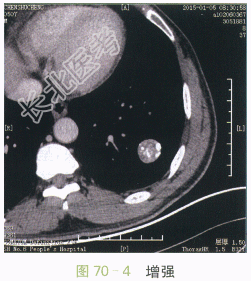

影像学资料如图70-1~图70-4所示。

图70-1~图70-4胸部CT平扫与增强:左肺下叶类圆形肿块,边缘光滑,瘤灶内斑点状钙化,呈爆米花样改变,增强扫描未见明显强化

读片分析:CT表现:左肺下叶类圆形肿块,直径约2.7cm,边缘光滑清楚,瘤灶内见多发的小斑片状钙化,呈爆米花样改变,增强扫描未见明显强化。